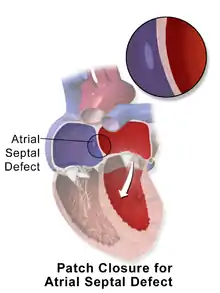

Surgical closure

Surgical closure of an ASD involves opening up at least one atrium and closing the defect with a patch under direct visualization.

Percutaneous closure of an ASD is currently only indicated for the closure of secundum ASDs with a sufficient rim of tissue around the septal defect so that the closure device does not impinge upon the superior vena cava, inferior vena cava, or the tricuspid or mitral valves. The Amplatzer Septal Occluder (ASO) is commonly used to close ASDs. The ASO consists of two self-expandable round discs connected to each other with a 4-mm waist, made up of 0.004– to 0.005-inch Nitinol wire mesh filled with Dacron fabric. Implantation of the device is relatively easy. The prevalence of residual defect is low. The disadvantages are a thick profile of the device and concern related to a large amount of nitinol (a nickel-titanium compound) in the device and consequent potential for nickel toxicity.